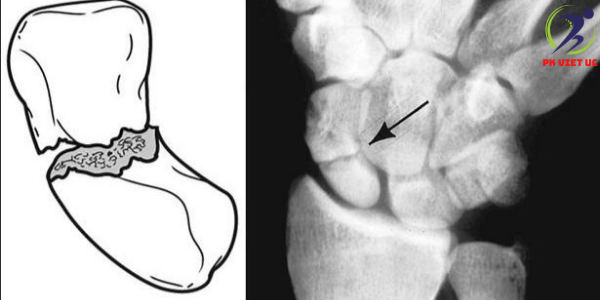

• Gãy xương di lệch. Trong loại gãy này, các mảnh xương đã di chuyển ra khỏi vị trí bình thường của chúng. Có thể có khoảng trống giữa các mảnh xương hoặc các mảnh có thể chồng lên nhau (Hình 2).

Hình 2: Gãy xương thuyền di lệch